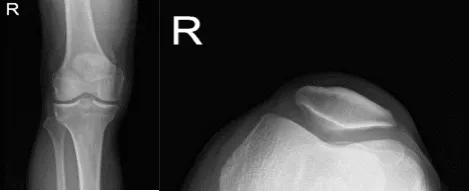

He was physically examined and an MRI was performed, which showed a complete tear of the quadriceps along with lateral meniscus tear, and partial tear of the ACL. The patient came to the emergency room due to intractable pain. We discussed treatment options and the patient opted for surgical management.

The patient underwent arthroscopic surgery. The procedures conducted were partial lateral meniscectomy, chondroplasty, ACL debridement and open repair of the quadriceps of the left knee. A left lateral entry portal was made and the scope was entered.

The scope was moved to the patellofemoral joint where trochlea grade 2 to grade 3 chondral damage was found. The chondral damage was debrided from the medial portal and followed by the lateral portal.

Copious lavage was performed. Arthroscopic pictures were taken and saved. The scope was removed. The knee was extended. The table was extended and a proper draping was performed. A midline vertical incision was put and centered over the superior pole of the patella.

The quadriceps tendon was found to be completely ruptured. The tendon was debrided. The stump of the tendon was over and the patella was removed. The bone was decorticated to fresh bleeding margins. three trans osseous tunnels were made and a silk tie was put for future use.